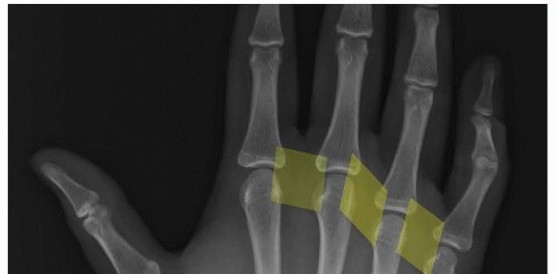

16 MIN READ Vascularized Bone Grafting and Capitate Shortening Osteotomy for Treatment of Kienböck Disease يناير 2023 Read More